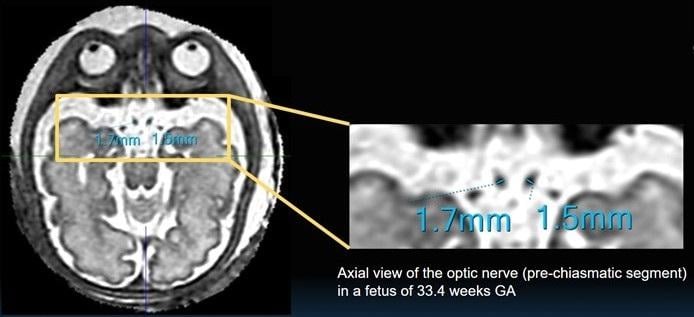

In Juang et al.’s retrospective study, all fetal MRI examinations performed at Phoenix Children’s Hospital between January 1, 2020 and August 1, 2022 were reviewed to find those with sufficient quality to reconstruct a 3D SVR image. First, a medical student reader examined the unprocessed fetal brain MRI—either from balanced turbo-field-echo or T2-weighted single-shot fast spin echo (T2 SSFSE) sequences—attempting FOP measurements where feasible. Then, 3D SVR reconstructions of fetal brain images were performed using a minimum of six T2 SSFSE imaging sequences. With that same reader next examining the reconstructed imaging and recording FOP measurements, two pediatric neuroradiologists with nearly a decade of experience read all FOP measurements. And to estimate the relationship between FOP measurements of normal fetuses and gestational age, nomograms were generated accordingly.

Specifically, a linear regression fit estimated the relationship between optic chiasm width (OCW) in millimeters in normal fetuses and gestational age (GA) in weeks as OCW = 0.11 × GA+2.0 (R^2 = 0.30); similarly, the relationship between pre-chiasmatic (PC) optic nerve width and GA was estimated as PC = 0.04 × GA +0.24 (R^2 = 0.34).